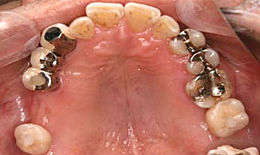

治療後

上顎

保存困難な歯を抜歯後、インプラントを2本埋め込んで、セラミックスクラウンを被せた

下顎

インプラントを2本埋め込んで、セラミックスクラウンを被せた